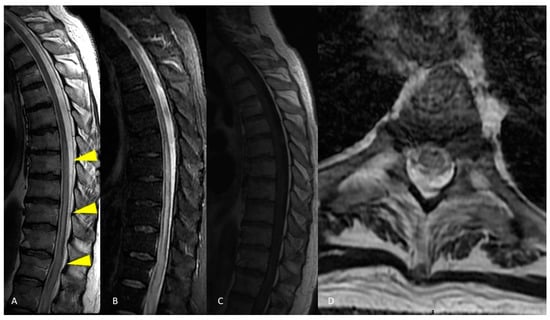

2.1. Case Presentation 1